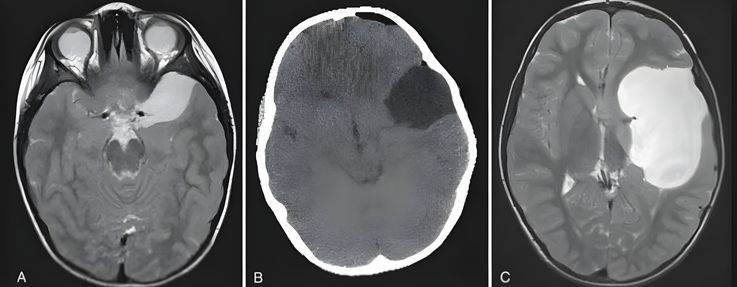

A Importância do Diagnóstico por Imagem

Para confirmar a presença do cisto e descartar outras patologias, o uso de exames de imagem é indispensável. A Ressonância Magnética (RM) é o exame padrão-ouro, fornecendo detalhes precisos sobre a localização e o volume da lesão. A Tomografia Computadorizada também auxilia na avaliação da densidade do cisto e na análise das estruturas ósseas do crânio.